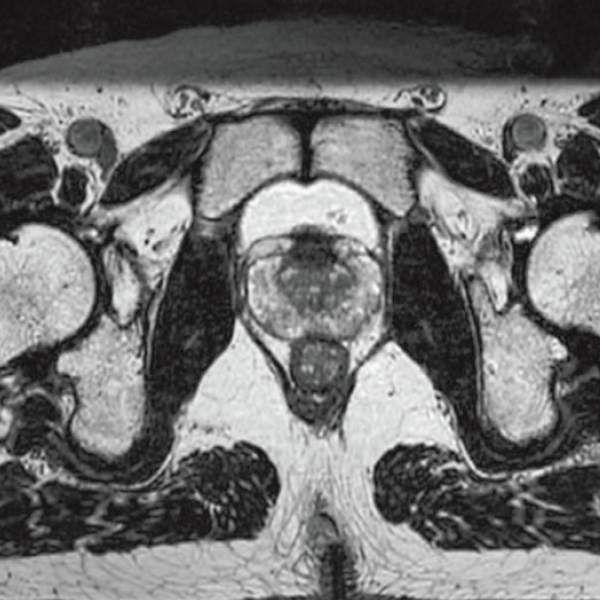

T2WI, 0.56×0.70×3.0mm, 2:28